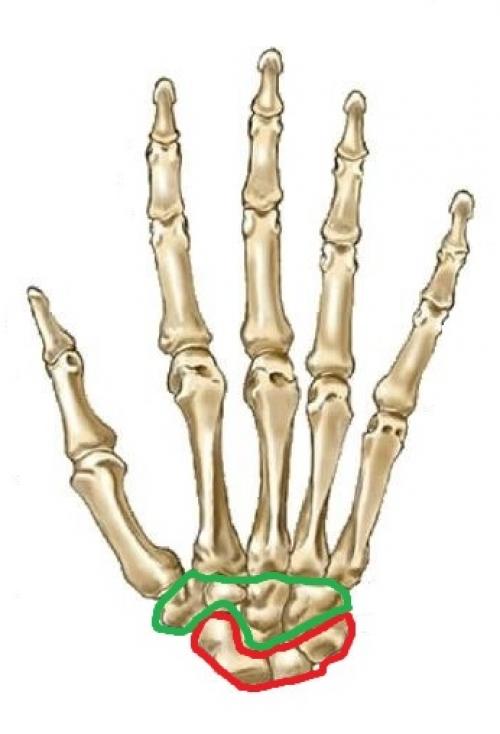

На этом рисунке я я выделил красным цветом проксимальный ряд костей запястья, а зелёным — дистальный.

Когда вам требуется найти какую-либо кость запястья, первым делом, вы должны отличать проксимальный и дистальный ряды. Давайте сориентируемся на анатомическом планшете, когда кисть руки нам показана условными пальцами вниз.

Первым делом найдём лучевую и локтевую кости. По лучевой кости мы находим сторону, где располагается большой палец, а по локтевой — сторону, где находится мизинец.:

После этого нам нужно отыскать на планшете кости запястья. Это очень легко сделать — восемь маленьких, плотных косточек сильно отличаются от всех остальных костей:

Далее следует разграничить дистальный и проксимальный ряды костей запястья. Этому мы уже научились в прошлом разделе, поэтому проксимальный ряд можно найти без труда (не забываем, что перед нами ладонь, которая расположена условными пальцами вниз):